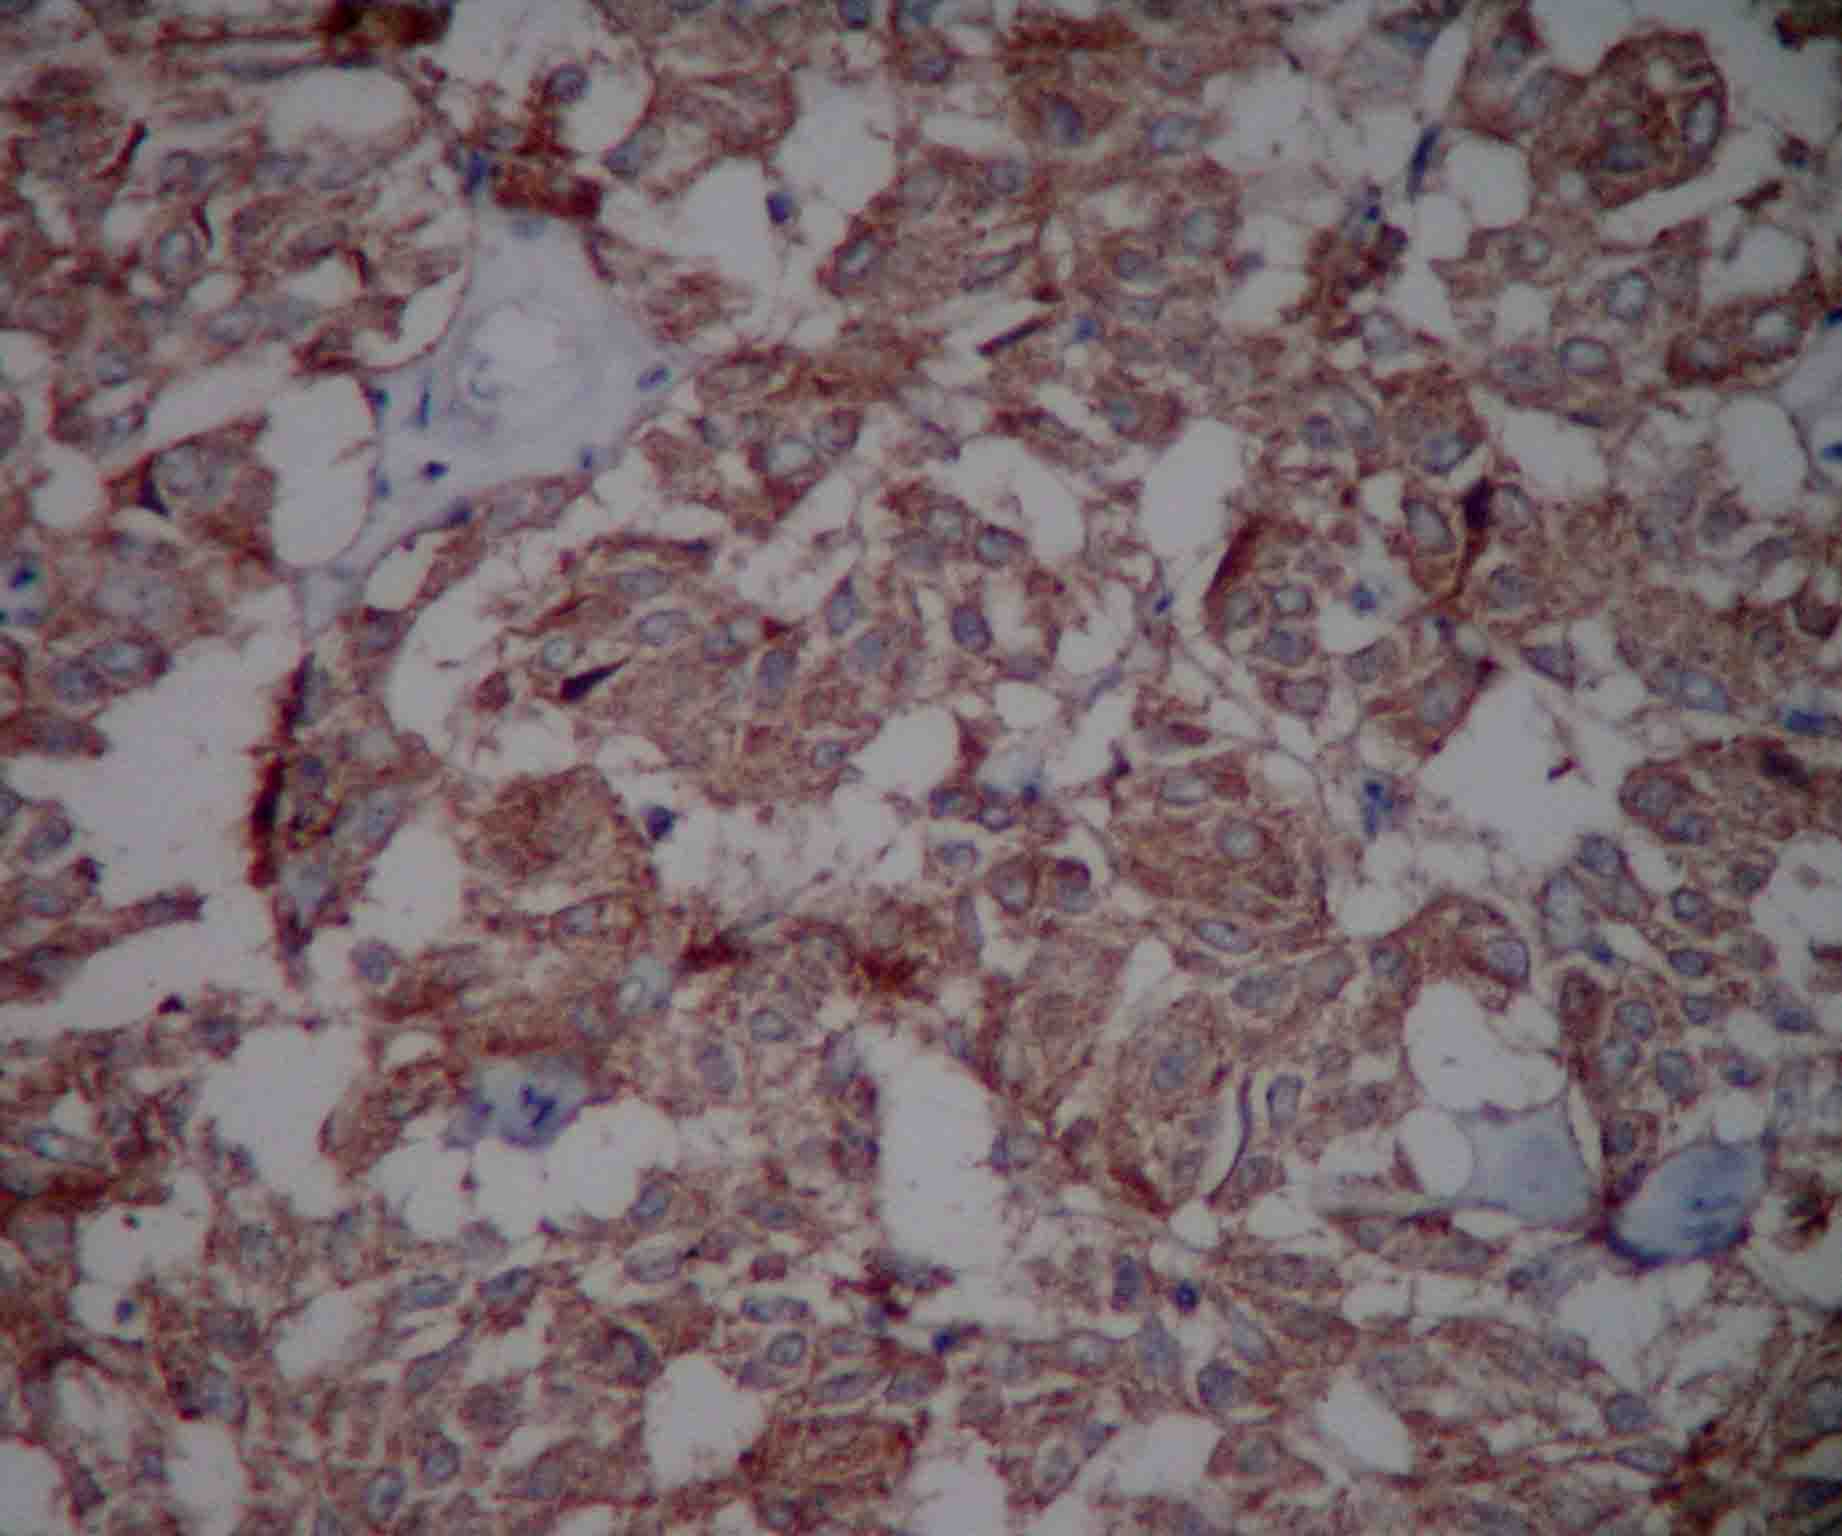

Carcinoid tumor is a serotonin-producing malignant tumor belonging to a class of neoplasms known as the neuroendocrine tumors. Carcinoid tumors of the lung are much less common and represent 1% to 2% of all lung cancers. The current classification of lung tumors recognizes bronchial typical carcinoid as low-grade neuroendocrine tumors. Symptoms are usually related to local compression and obstruction of the bronchial tree. Preoperative diagnosis is usually obtained without bronchoscopic biopsy. The authors report the case of a woman with typical carcinoid tumor in the left lower lobar bronchus, next to the secondary carina. It was treated with bronchoplastic resection, and associated to lymphadenectomy. The complete surgical resection remains the only therapy with curative intent in the majority of patients. Local relapse can be treated successfully with surgery, whereas distant metastases have a poor prognosis even after chemotherapy.Downloads

- cromogranina.jpg (Português (Brasil))

- Sinaptofisina.jpg (Português (Brasil))